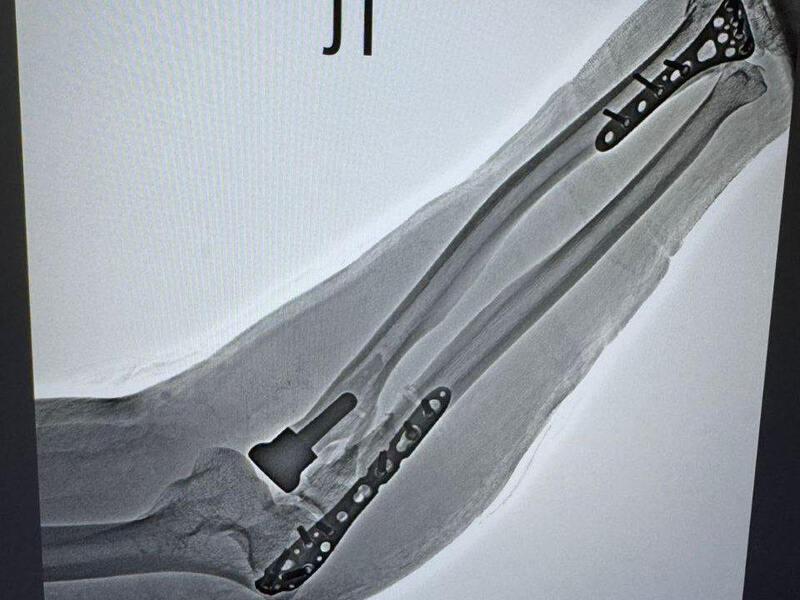

Первой пациентке 66 лет — у неё диагностировали оскольчатый перелом головки лучевой кости. Второй случай сложнее: 55-летняя женщина получила множественные травмы — перелом метаэпифиза левой лучевой кости, перелом локтевой кости в верхней трети и оскольчатый перелом головки лучевой кости.

При переломах костей хирурги обычно фиксируют отломки металлическими пластинами — операция называется остеосинтезом. Методика отработана и эффективна в большинстве случаев.

Но при оскольчатых переломах головки лучевой кости, когда она дробится на множество фрагментов, ситуация иная. Собрать мелкие осколки и надёжно зафиксировать их пластиной практически невозможно. Требуется другой подход.

Решение: эндопротез

Врачи выбрали протезирование головки лучевой кости. Суть операции в следующем:

- удаляют повреждённые костные фрагменты;

- формируют костномозговой канал в проксимальном отделе лучевой кости;

- устанавливают эндопротез из биосовместимого материала.